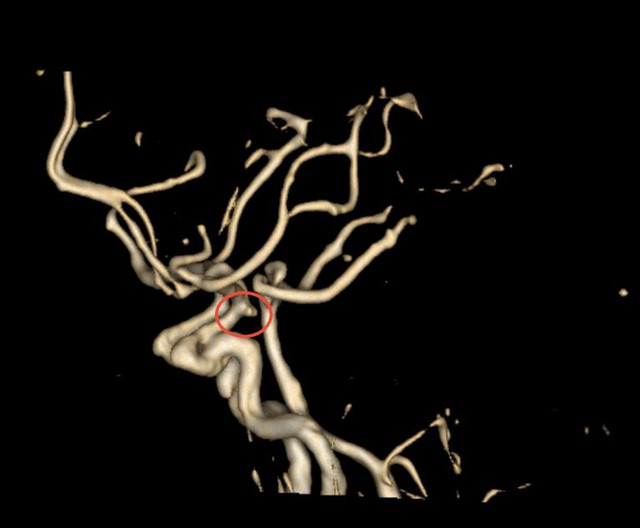

Vị trí túi phình trên phim CTA. Ảnh: BVCC

Với chẩn đoán trên, bệnh nhân được tiến hành chụp CT mạch máu não (CTA) và phát hiện một túi phình kích thước 7-8 mm ở động mạch cảnh trong đoạn thông sau, nằm tại một vị trí tương đối khó quan sát, gần sàn sọ và có dấu hiệu vỡ.